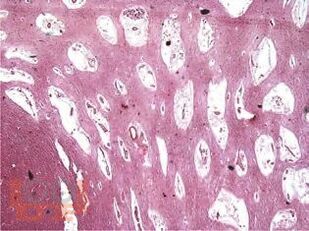

В монографии изложены современные представления об этиологии, патогенезе, эпидемиологии, патоморфологии сосудистых когнитивных нарушений, а также других заболеваний, сопровождающихся нарушениями когнитивных функций; подробно рассмотрены вопросы классификации, клинической картины, нейропсихологической, лабораторной и инструментальной диагностики, принципы, направления и схемы терапии.